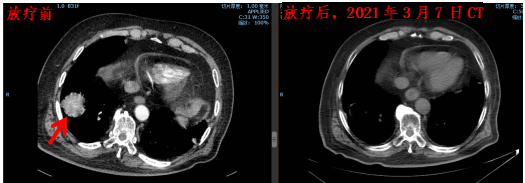

下面是崔大爷放疗前和放疗后近2年2021年3月的CT对比。(左图为放射前,右图为放疗后)

崔大爷总共放疗了25次,放疗后复查CT发现原来的肺部肿瘤竟“神奇”消失了,随后崔大爷定期复查。

肿瘤放疗科接诊后仔细询问病史、阅片、心肺功能情况,全科讨论后为患者制定了专属的放疗方案。先进的CT模拟定位、图像引导调强放疗,能够更精准的治疗病灶。误差控制在3毫米以内。给的剂量既能“杀死”肿瘤,又能最大程度得保护心肺等周围器官。放疗过程中崔大爷也没什么不舒服。

崔大爷在医院做了肺穿刺,病理结果是肺鳞状细胞癌。崔大爷当年已经77岁了,除了上面提到的几种疾病外,肺功能也不好,胸外科医生认为崔大爷身体不能耐受手术,于是,2019年4月在肿瘤放疗科做了单纯放疗。

崔大爷是一个胖老头,2018年底有点咳嗽,做CT体检发现右肺长了个“东西”。由于崔大爷有50多年的精神疾患,还有糖尿病和心脑血管疾病等,咳嗽也不严重。也没有其他不舒服。家属也怕崔大爷知道了有精神负担,家属选择了等待观察。5个月后再做CT时,发现这个肿瘤已经长到44毫米×44毫米,也就是肿瘤已经长到鸡蛋大小了。